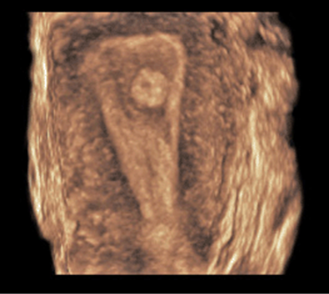

FIGURE 8–29. Two separate endometrial cavities and uterine horns. (Courtesy of Philips Healthcare.)

Three-dimensional sonography affords depiction of the configuration of the uterine fundus. With a septated uterus, the fundal contour is smooth, whereas with bicornuate and didelphys, a sharp cleft is seen.